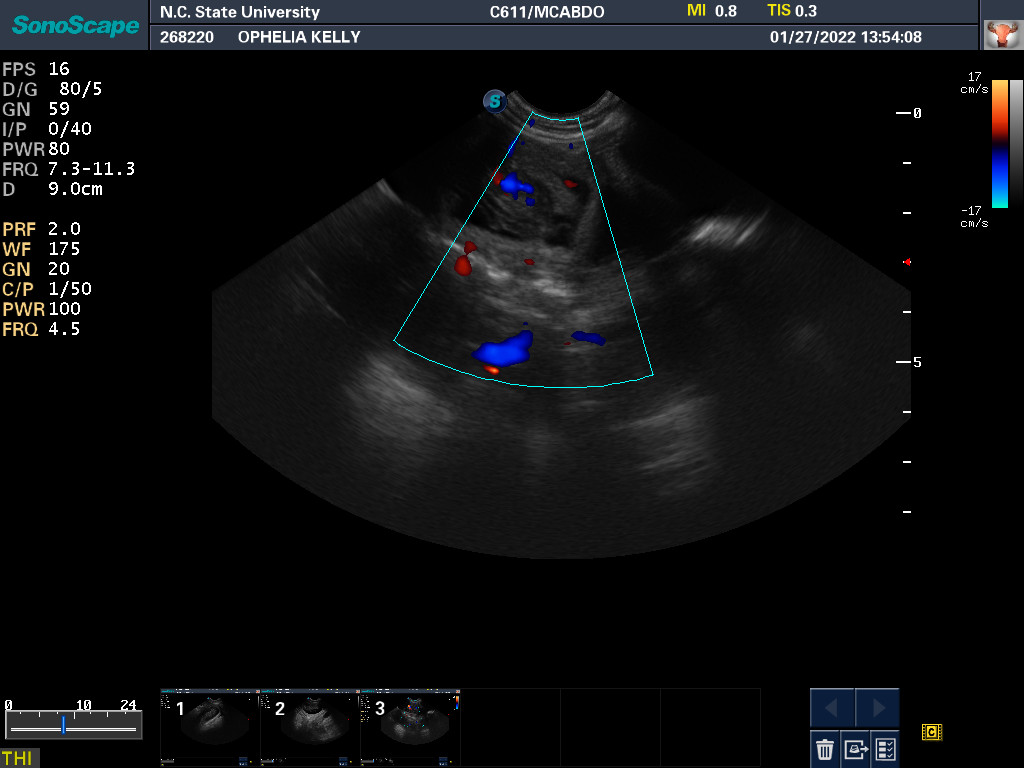

22 Feb

This morning I took Ophelia to NC State. Yesterday Ophelia's progesterone was around 8 ng/mL. Today it is around 4 ng/mL. So no puppies today. What my repro vets want to see is around 2 ng/mL. They also ultrasounded the puppies looking for GI movement and checking their heartbeats. On the way home I stopped at a grocery store and stocked up on cottage cheese and plain whole yogurt, which will be necessary when the puppies come.